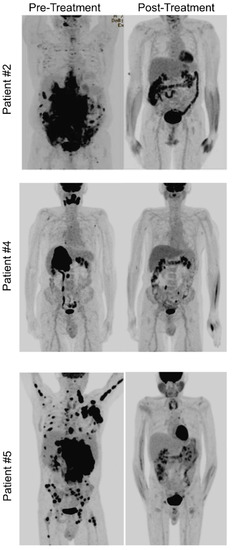

| 2 | 73 | M | African American | HIV/AIDS CMV, EBV | 6 cycles of EPOCH- Dara added on c2 (1 dose c2, 2 doses from C3–6) Vincristine omitted on C6 | 25 mo ongong | CR at interim scan after 4 cycles | Neuropathy- held vincristine on C6 | CD138++ |

| 4 | 79 | M | White | None | 6 cycles DARA- R-EPOCH alternating with IT MTX At relapse R-DHAX- Daratumumab | 4/2021–7/2021 so 3 mo | CR after 4 cycles of DARA-R EPOCH | Neutropenic fever × 1 episode | Sparsely CD138+, CD38+ |

| 5 | 48 | M | Hispanic | HIV/AIDS (CD4 of 4 VL 191K) EBV | Dara-EPOCH × 6 cycles LP with HD MTX × 3 cycles Dara- HD MTX × 2 | PR after 2 cycles | Peripheral neuropathy Anemia requiring transfusion Difficulty clearing pre-exisiting infection (i.e., Norovirus causing critical hypoK and hypoMg from chronic diarrhea and malnutrition requiring treatment with nitazoxadine) | CD138++, | |